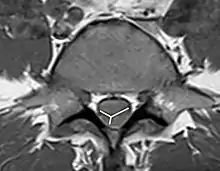

Owl-eyes sign exhibits bilaterally symmetric circular to ovoid foci of T2-weighted signals in anterior horn cells.

As the non-contrast CT and spine CT angiography are ineffective in imaging modalities, doctors use MRI to confirm the diagnosis. MRI findings, including pencillike hyperintensities on T2-weighted sagittal images and "owl's eyes" or "snake eyes" sign on T2 axial images, indicate the infarction is predominately in the watershed area of the gray matter of ventral horn (anterior spinal artery infarct).[10] Also, posterior paramedian triangular hyperintensity in T2 hyperintensity indicates posterior spinal artery infarct. On a T1 sequence, we may also observe a cord expansion and a decreased signal.[18] However, traditional MRI may show no abnormality especially for those patients in the acute phase.[8] DWI is very sensitive for early detection of spinal cord infarction and shows a typical high signal intensity.[19]